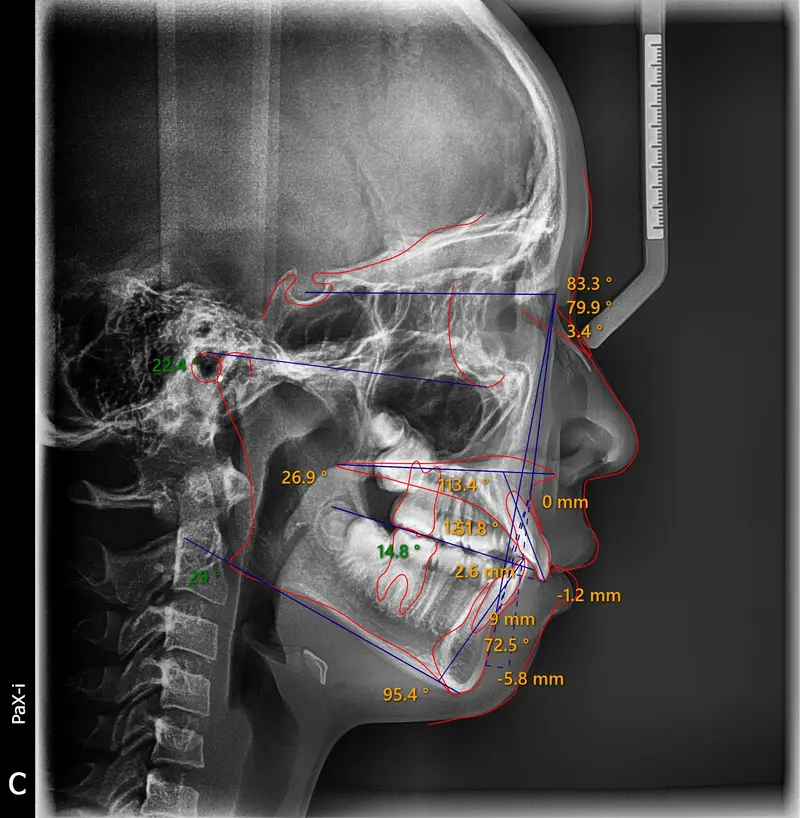

Phase 1 Early Intervention 12 Months

The Diagnosis

Severe crowding with blocked-out permanent teeth. The jaw size was insufficient to accommodate the erupting adult teeth, leading to significant rotation and displacement.

The Engineering

By intervening early, we utilized rapid palatal expansion to develop the arch width. This created the necessary space for the permanent teeth to erupt naturally, avoiding the need for future extractions.